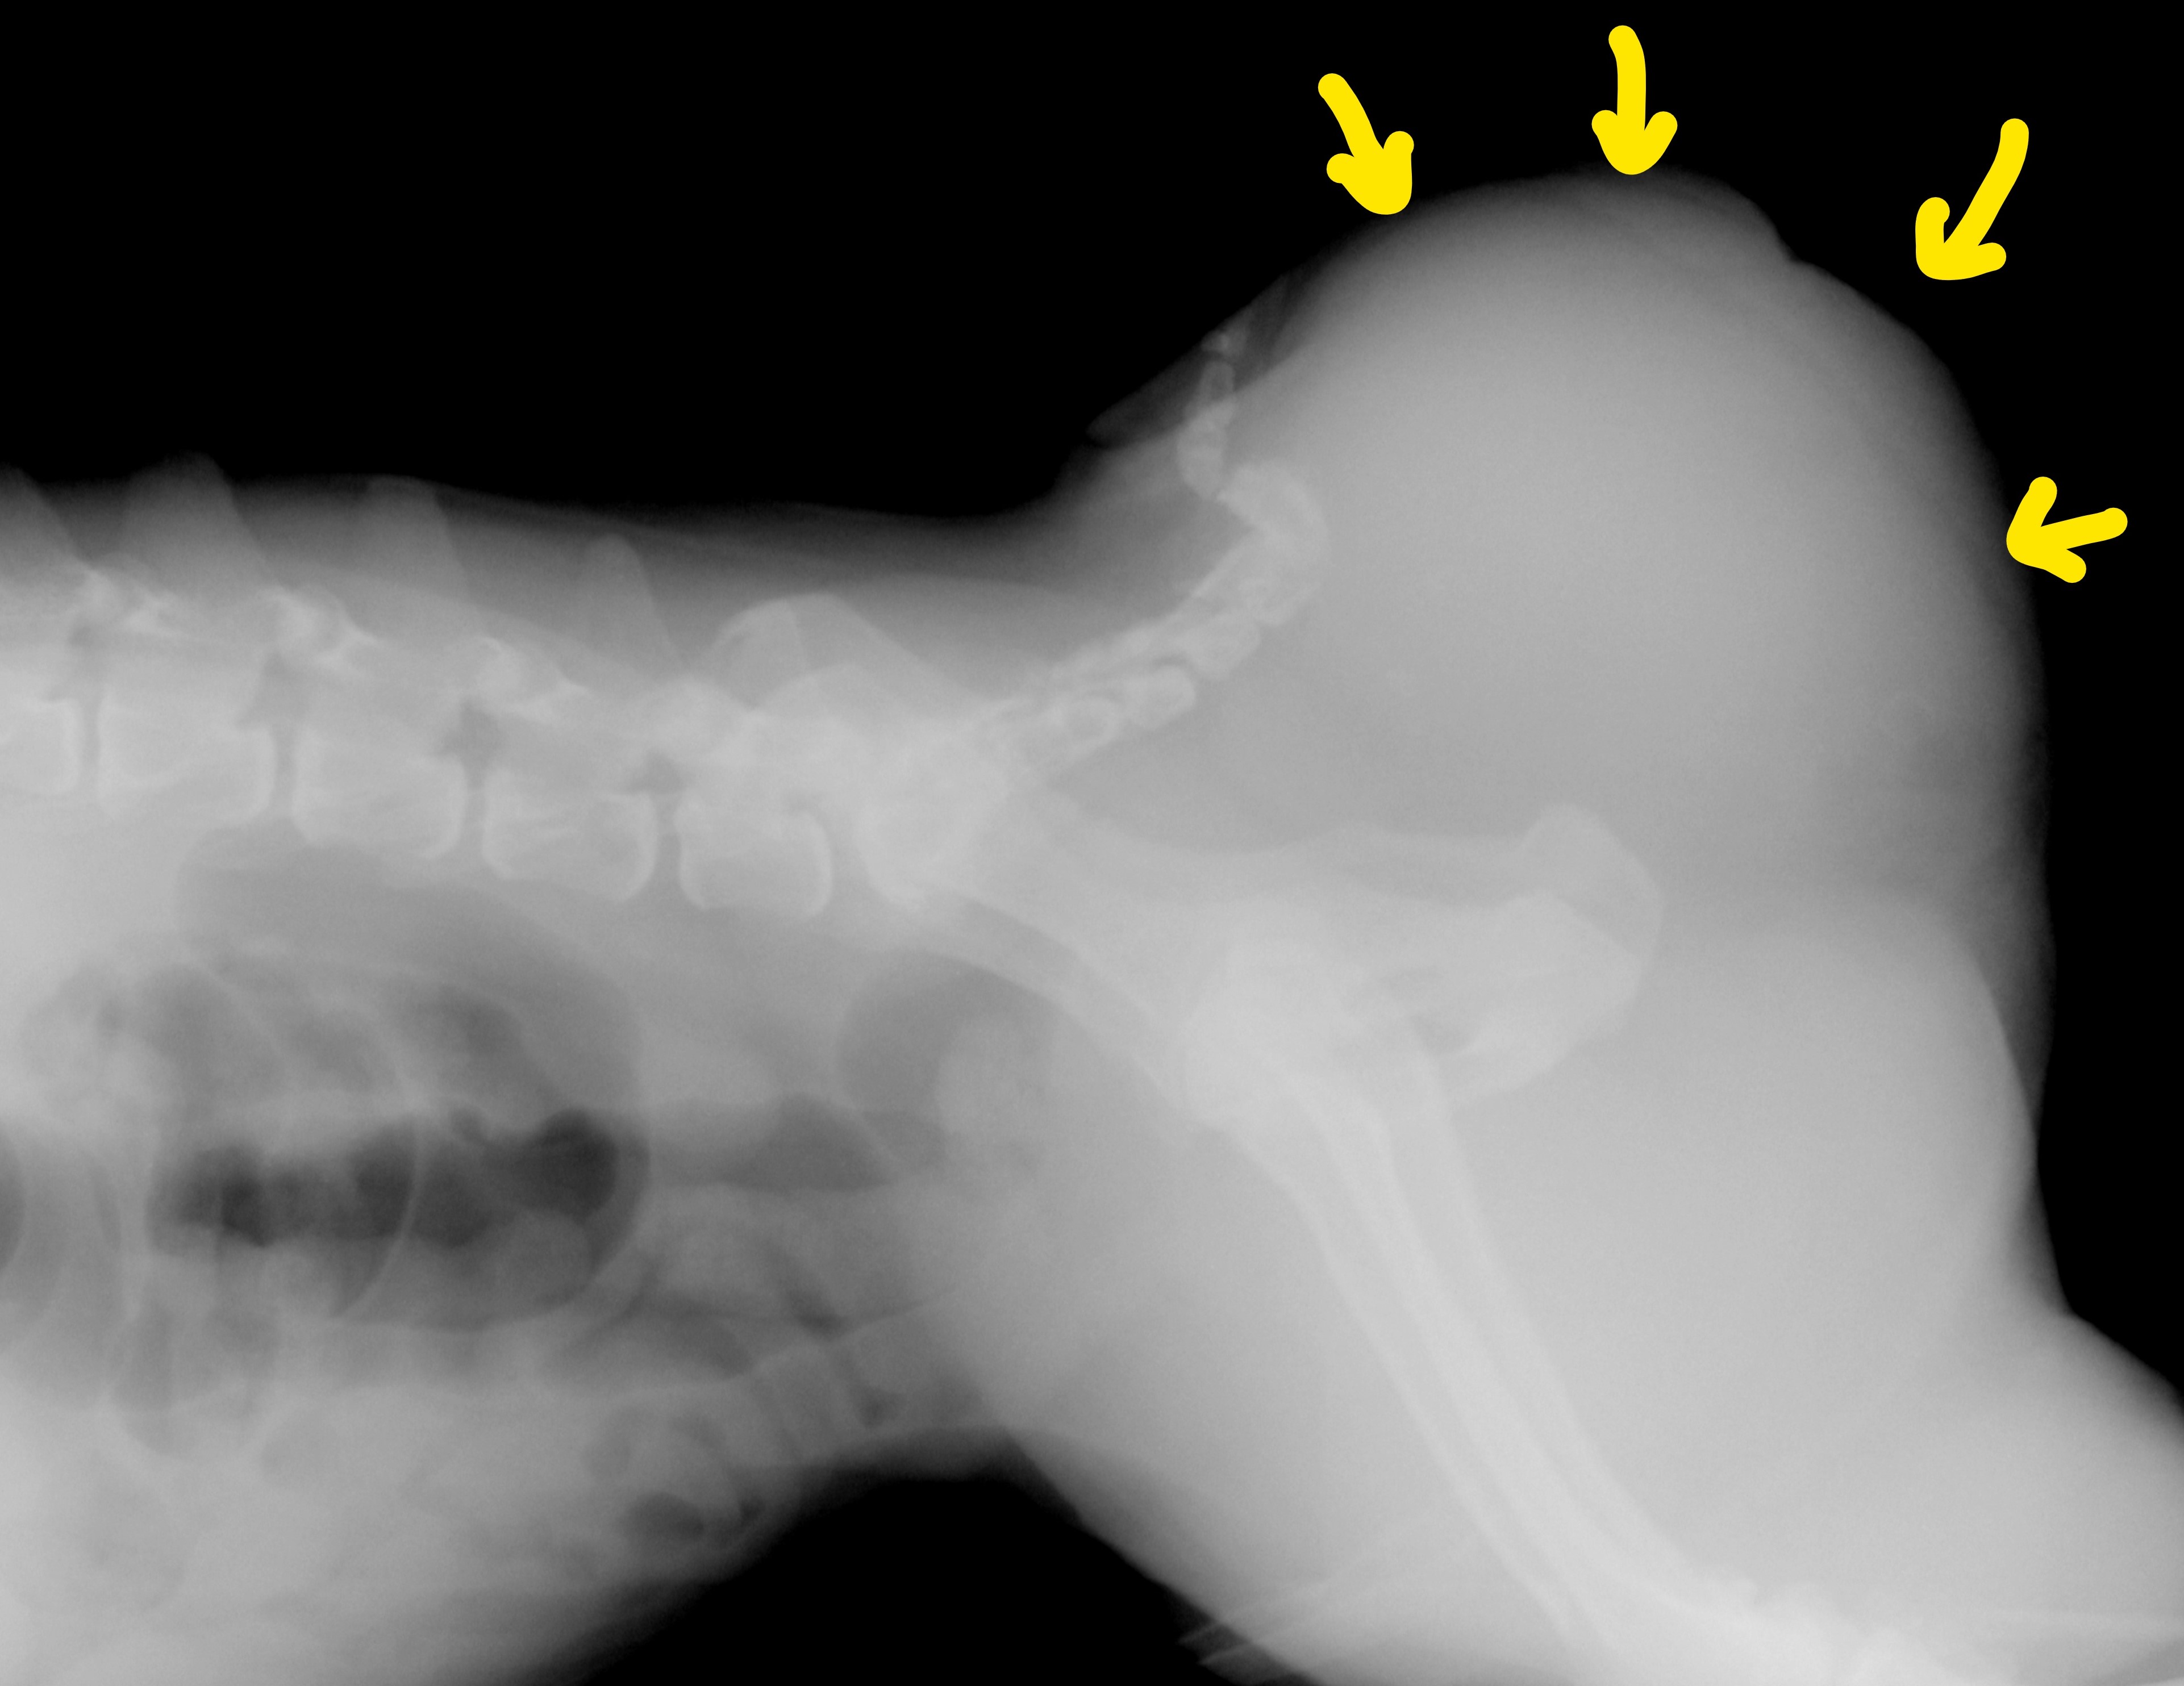

レントゲン画像:会陰部(矢印)が重度に膨らんでいる

左右両方の会陰部(肛門周囲)が重度に膨張し、レントゲンおよび超音波検査にて右側に膀胱が嵌頓(ヘルニア内に膀胱が入り込んだ状態)していました。左側には炎症による漿液貯留を認めました。